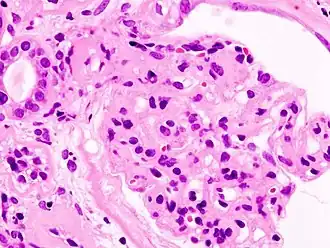

Imagem microscópica da glomeruloesclerose diabética, principal causa da síndrome nefrótica em adultos

Causasglomeruloesclerose segmentar e focal, nefropatia membranosa e doença de lesão mínima, lúpus, diabetes[1][2]